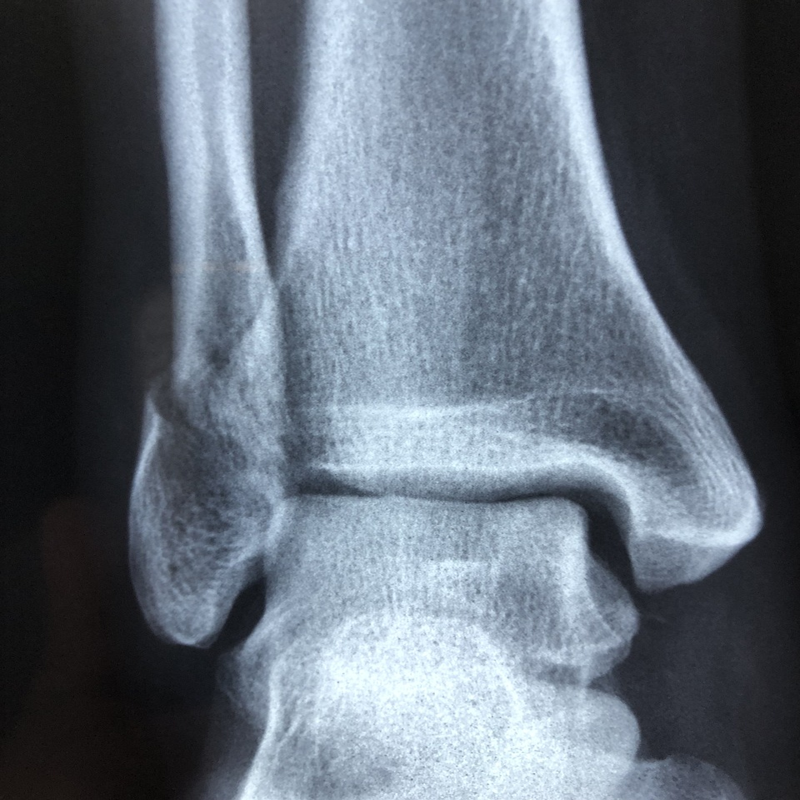

5. 외상:

발목을 다치면 혈관이나 조직이 손상되어 혈액이나 림프액이 새어 나와 발목이 부을 수 있습니다.

- 발목 염좌

- 골절

- 타박상